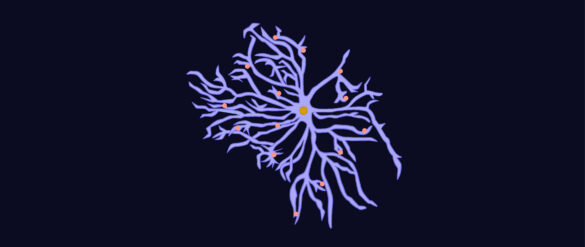

Astrocitos: Su papel clave en la memoria

Los astrocitos, células gliales en forma de estrella, han sido tradicionalmente considerados elementos de soporte en el sistema nervioso central. Asimismo, investigaciones recientes han demostrado que también desempeñan un papel esencial en procesos cognitivos complejos, como la memoria. Desde la regulación sináptica hasta la plasticidad…